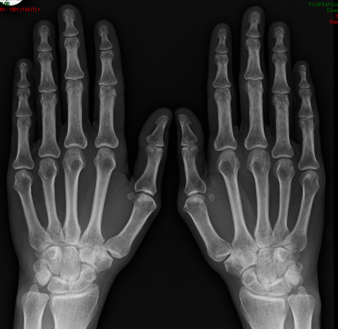

Rhumato : PR, psoriasis, PPR